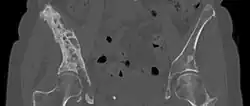

-

CT scan chest: Bone cancer in back and ribs, spread from lung cancer. -

CT scan: Parotid gland cancer spread to hip. -